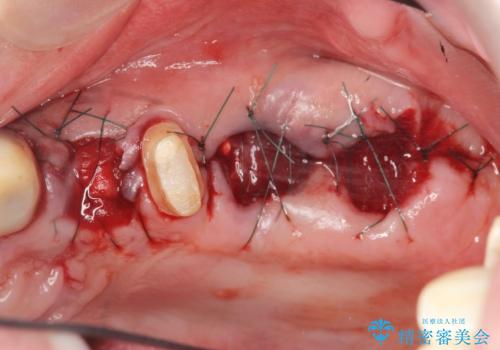

骨の造成を行った上顎インプラント治療

精密検査の結果、重度の歯周病が認められ大きな骨の吸収を認めました。

予後の悪く保存の難しい歯を抜去し、骨の造成を含んだインプラント治療を計画します。

骨の造成を行ったことで歯肉のラインは平らになり、清掃性の高い歯周環境を作り出すことができました。